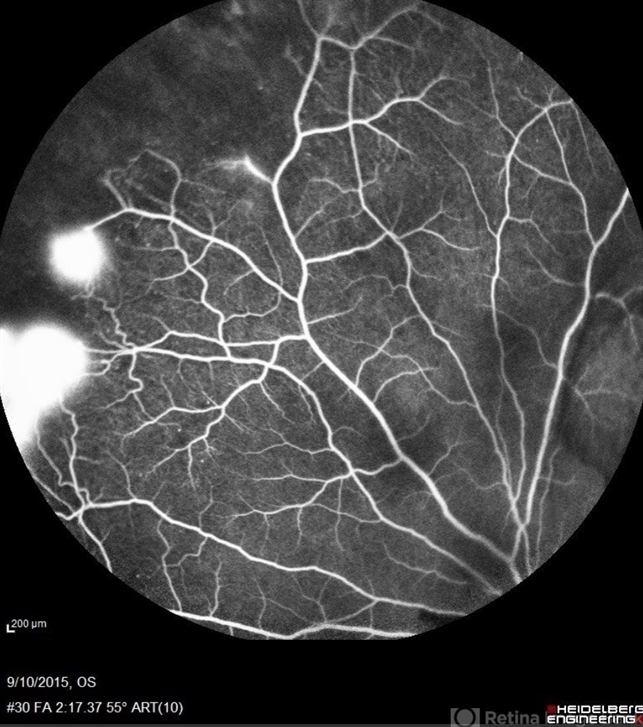

- Sickle Cell Retinopathy

- sickle cell retinopathy, peripheral retinal neovascularization, sea fan

- Scanning laser ophthalmoscope

- Angiography showed normal vessels posteriorly but severe capillary drop out throughout the periphery OU with scattered severe neovascularization at the edge of the capillary drop out peripherally.